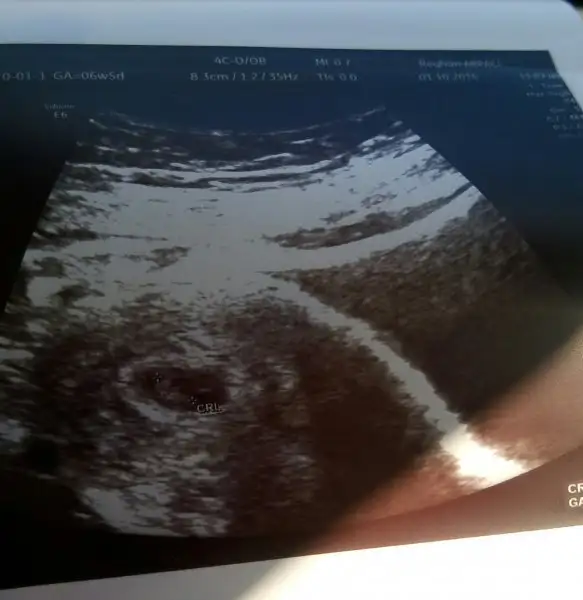

Hazirandaki gebeliğim sonlandı maalesef.pıhtılaşma olmuş ve bebeğimin kalbi durmuş.şimdi allahın izniyle tekrar hamileyim kan suşandırıcı iğne kullanıyyorum.yorum yaparmısınız usg lere.2 side karından .ilk resim 7 hafta 2.si 6+3.

Allah bağışlasın canım.evet karından,bir kızım var 7 yaşında buda 2. Miz :) kızıma kızkardeş mi erkek kardeş mi gelecek bakalım.12.haftada gideceğim tekrar belkş Dr bi tahmin yapar